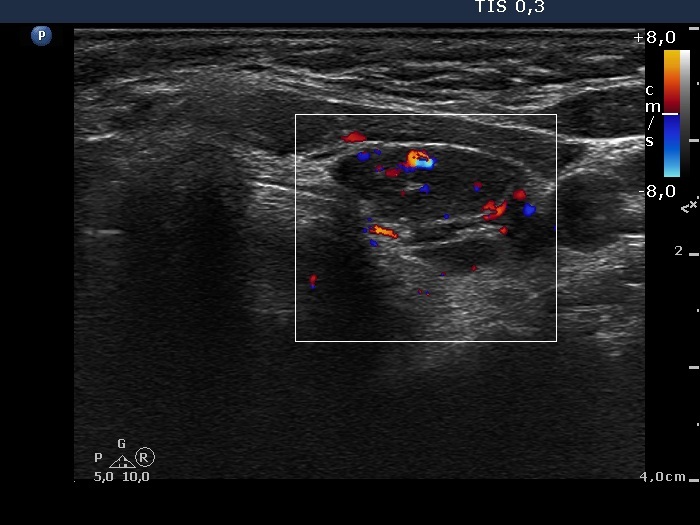

Discrete lesion or nodule in Hashimoto's thyroiditis - case 16 (797) (ultrasonographic picture 6)

Upper part of the left lobe, transverse view, color Doppler mode. The vascularization is not specific.